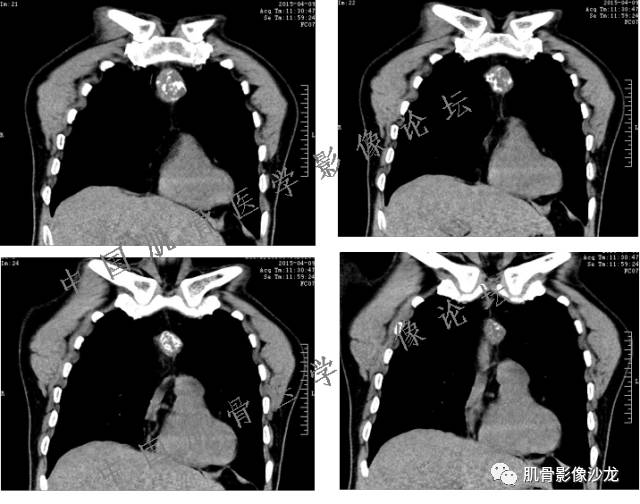

1、软骨肉瘤可以有膨胀性骨质破坏(病例3,4),可以有溶骨性骨质破坏(病例2),局部皮质因为破坏变薄,中断 ;

2、软骨基质T2WI高信号,软骨小叶分叶状,也就会出现高老师提到的骨内膜扇贝形压迹。一般认为骨内膜扇贝形压迹超过骨皮质厚度的2/3是软骨肉瘤在长管状骨的特征性表现。如上图。3、软组织肿块或肿胀;

4、 钙化,环形,弓形,边缘模糊 ;

5、增强后进行性延迟,不均匀分割状强化, 会强化的纤维间隔,软骨小叶不会强化,关于老师们说到的钙化,软骨肉瘤不一定会有钙化 。

郝大鹏: 软骨小叶常规时间不强化,延迟几个小时会强化。常规时间内强化的是小叶间隔